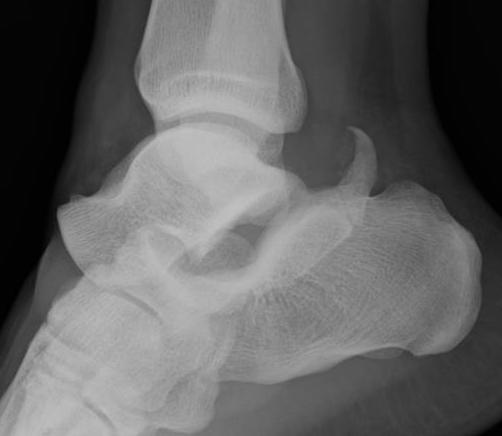

Medial subtalar dislocation

1. Medial

- calcaneum dislocated medially

- more common

- forced inversion in plantar flexed position